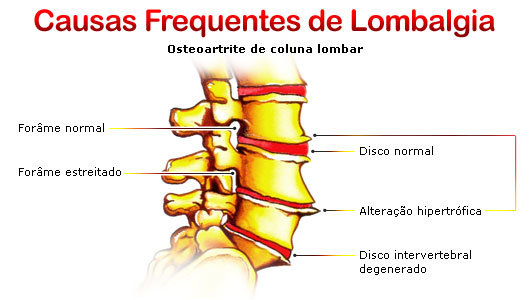

Existem diversas doenças ósseas que independem do trauma, como o câncer ósseo, luxações congênitas e deformidades ósseas que necessitam de tratamento médico. As hérnias de disco, causadoras de dores intensas na coluna, podem ser operadas tanto por ortopedistas como por neurocirurgiões, dependendo de sua formação.